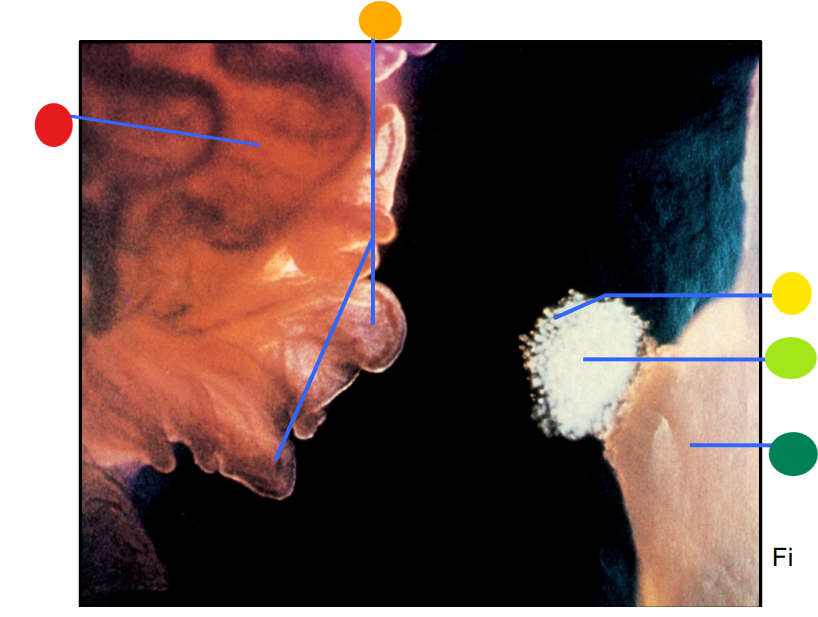

red

infundibulum

orange

fimbriae

yellow

cumulus oophorus

light green

oocyte

dark green

ovary

How is the egg and culmulus oophorus drawn into the infundibulum after the rupture of a mature follicle?

via ciliary action